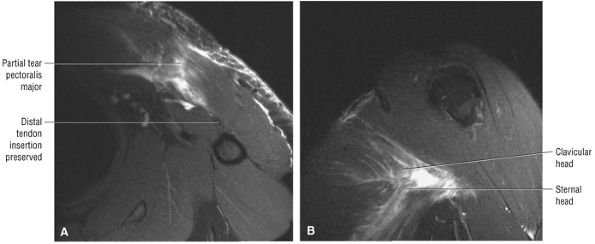

FIGURE 8.102 ● (A) The anterior undersurface of the acromion and the coracoacromial ligament form the coracoacromial arch. The subacromial subdeltoid bursa facilitates the passage of the rotator cuff and proximal humerus under the coracoacromial arch. (B) A superior axial image shows the anterior-to-posterior extent of the coracoacromial (CA) ligament perpendicular to the supraspinatus tendon. The fluid in the subacromial-subdeltoid bursa represents fluid between two serosal surfaces in contact with each other. One serosal surface is contributed by the undersurface of the coracoacromial arch and deltoid, and the other serosal surface is on the bursal side of the cuff.

|

![]() |

FIGURE 8.103 ● Pseudospur. The normal broad attachment of the coracoacromial ligament to the inferior surface of the acromion is shown on (A) T1-weighted coronal oblique and (B) sagittal oblique images. The low-signal-intensity acromial cortex (black arrows) and adjacent coracoacromial ligament and lateral slip of the deltoid attachment (white arrows) give the false impression of a small subacromial spur in the coronal plane. This pseudospur should not be misinterpreted as impingement; otherwise, unnecessary acromioplasties may be performed on patients with a normal coracoacromial ligament attachment and no associated acromial spurs.

-